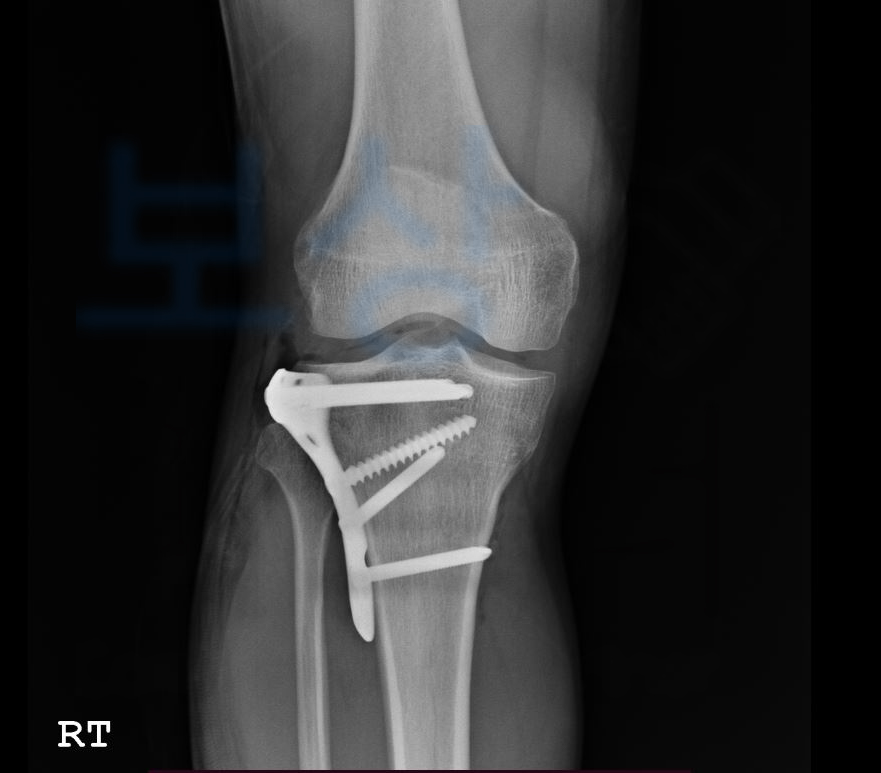

정@@님은 건설 현장에서 자재가 무릎에 떨어져 무릎뼈가 골절되는 사고를 당하셨습니다.

위 사고로 정@@님은

관혈적 정복 및 금속내골정술, 관절경술 즉 핀 고정술을 하셔야 했는데요,

위와 같이

무릎뼈 골절로

슬관절의 기능 장해 12급

인정받았습니다.